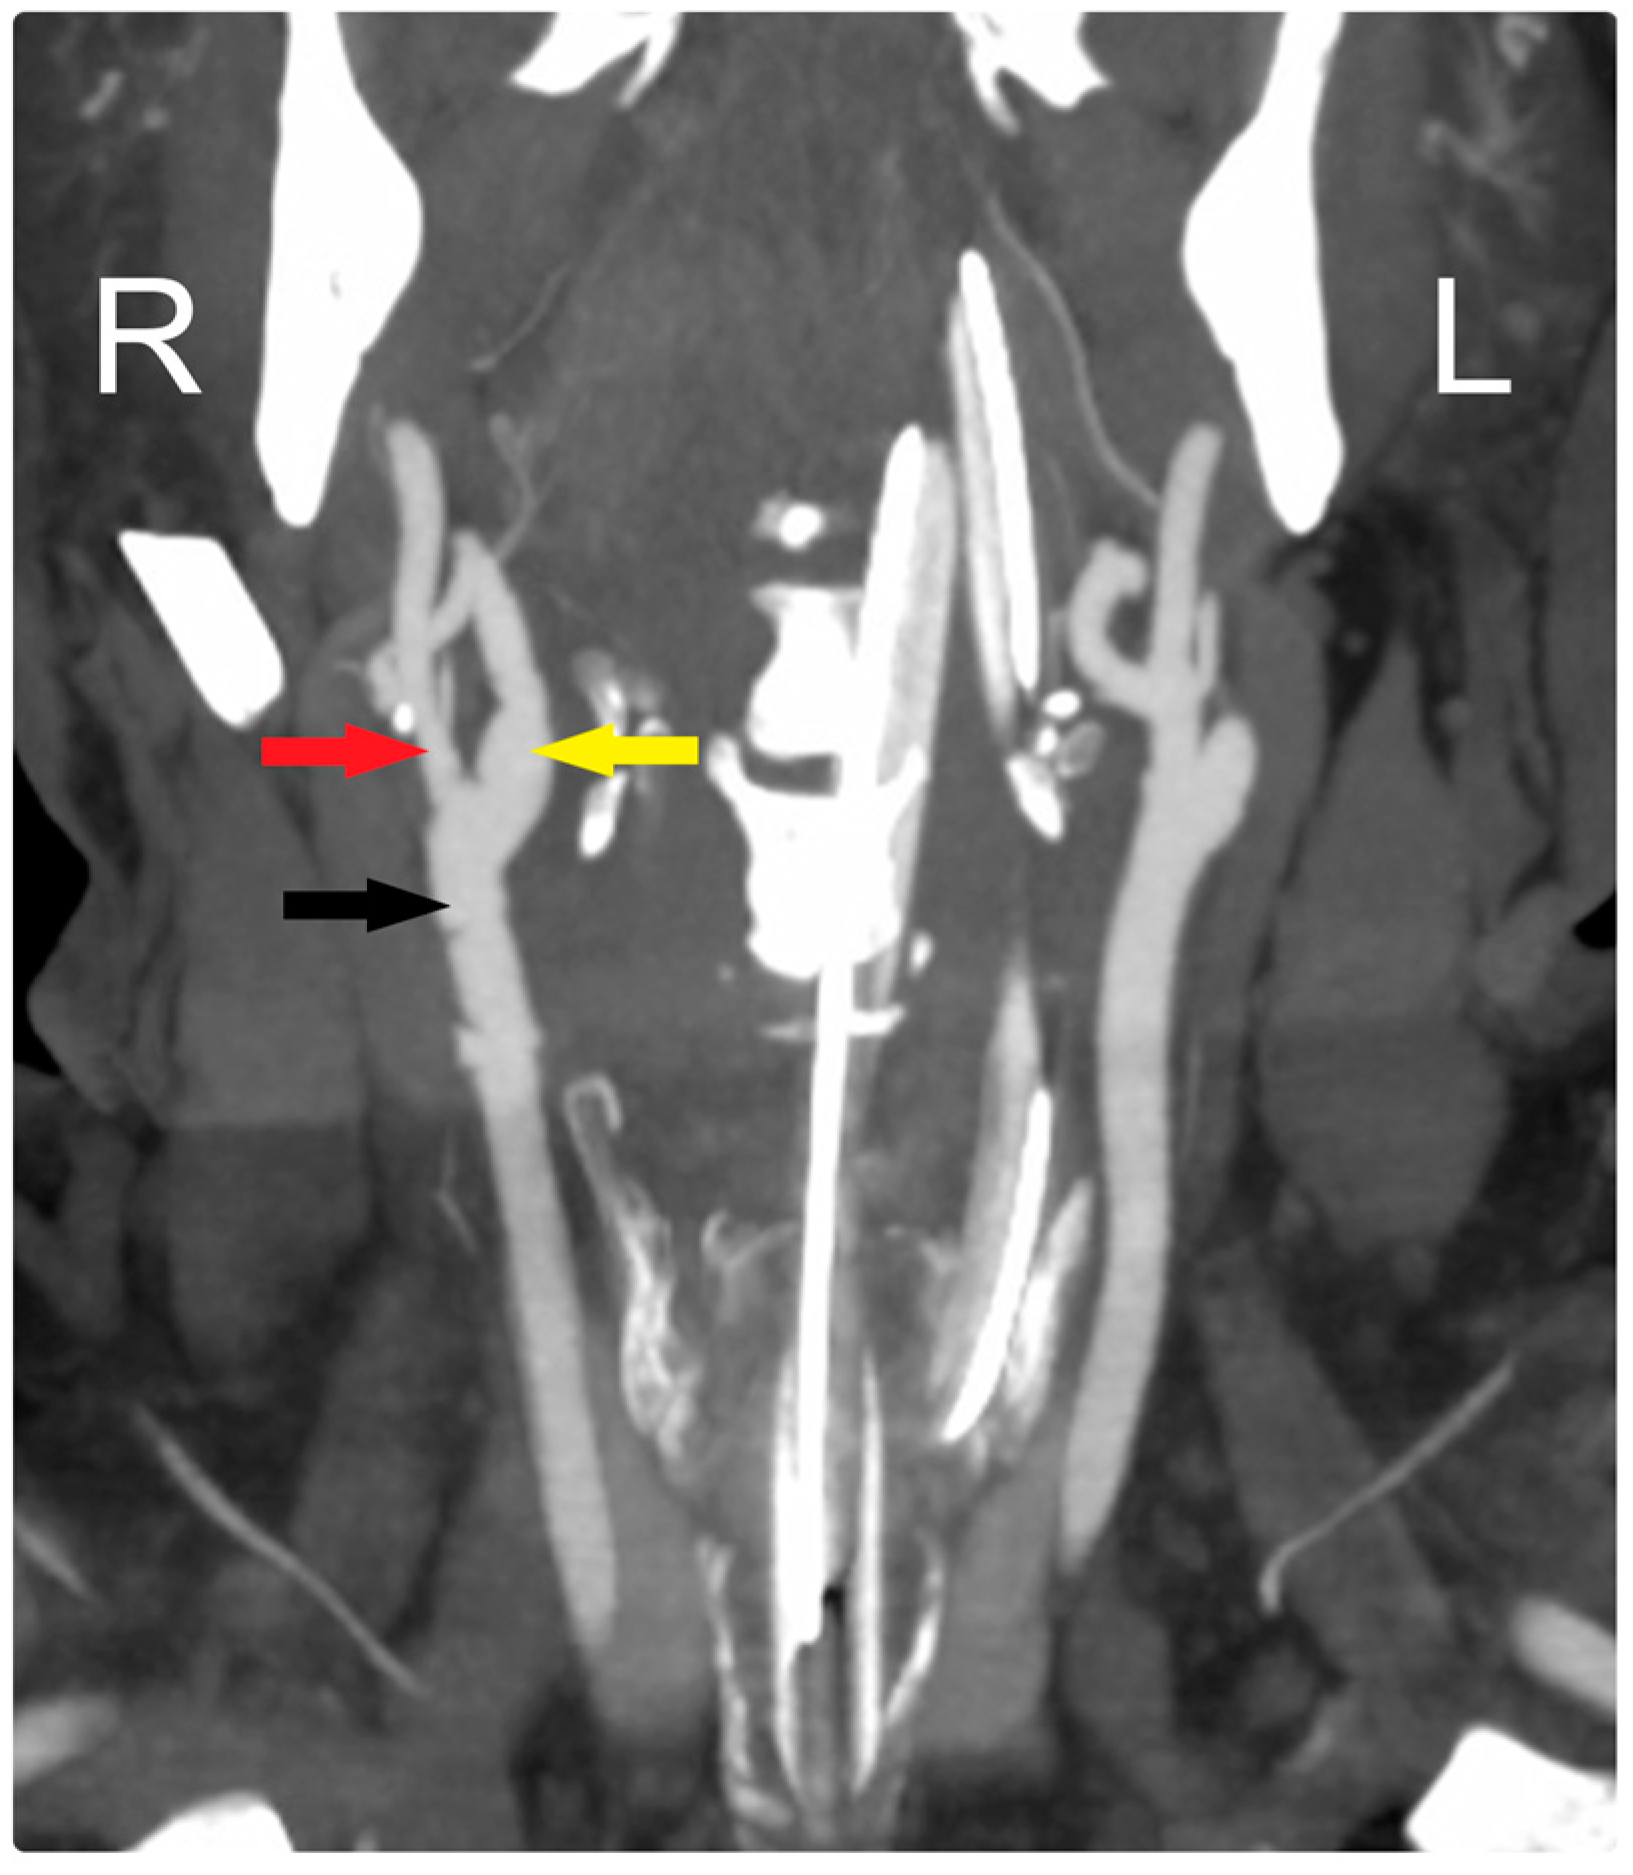

At his early postoperative period, a CTA scan of the head confirmed the patency of the CCA and ICA (Figure 3). Over a one-and-a-half-year follow-up period, the patient became neurologically intact and was functioning independently, with the arteries remaining patent throughout this time.

Figure 3.

Early postoperative CTA shows patency of all arteries: CCA (black arrow), ECA (red arrow), and ICA (yellow arrow). R: Right, L: Left.